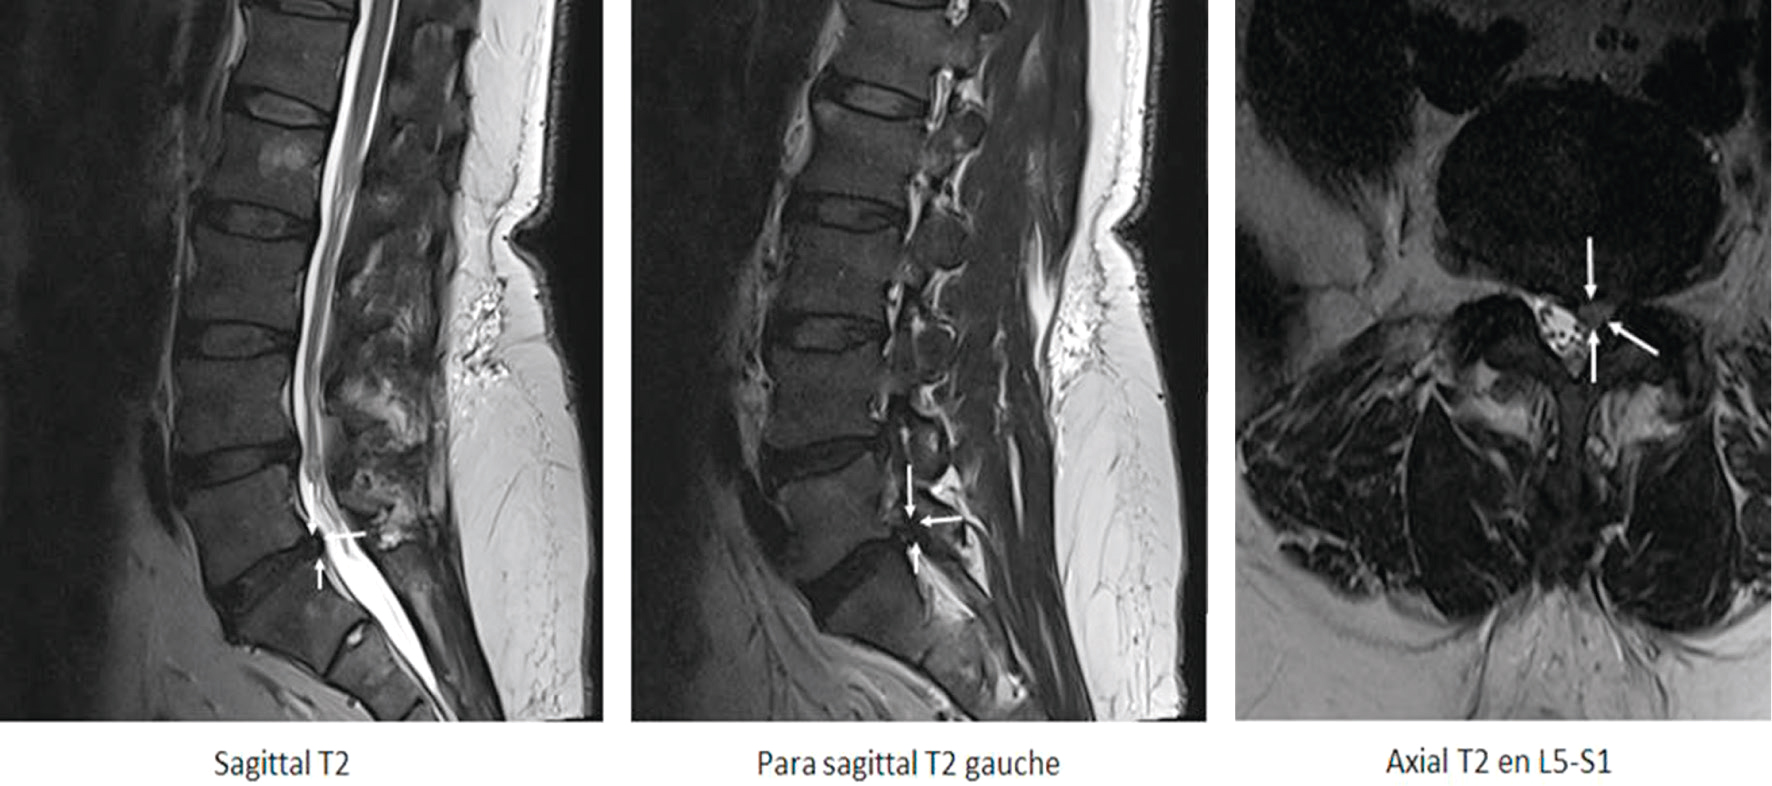

Hernie discale L5-S1 gauche comprimant la racine S1. Conflit foraminal gauche visible en sagittal et axial T2.

Fig. 8.8 Figure Hernie postérolatérale gauche L5-S1 en hypersignal modéré (potentiellement exclue), conflictuelle avec l’émergence durale de la racine S1 gauche (flèches blanches).

Les images en pondération T2 montrent une hernie discale postéro-latérale gauche au niveau L5-S1. Sur la coupe sagittale, on observe une saillie discale en hypersignal modéré qui modifie le contour postérieur du disque, laissant supposer un fragment possiblement exclu. L’image para-sagittale gauche met en évidence l’extension de cette hernie vers le foramen, dans le prolongement du trajet de la racine S1. Sur la coupe axiale, la hernie entre clairement en conflit avec l’émergence durale de la racine S1 gauche, comme l’indiquent les flèches blanches, confirmant l’origine du conflit disco-radiculaire. Ce contact étroit entre la racine et le fragment discal hernié est responsable d’une compression foraminale unilatérale gauche, expliquant les symptômes d’irradiation douloureuse ou de déficit sensitivo-moteur en territoire S1. L’aspect global évoque une hernie à composante extrudée, localisée à gauche, avec effet compressif direct sur la racine adjacente.